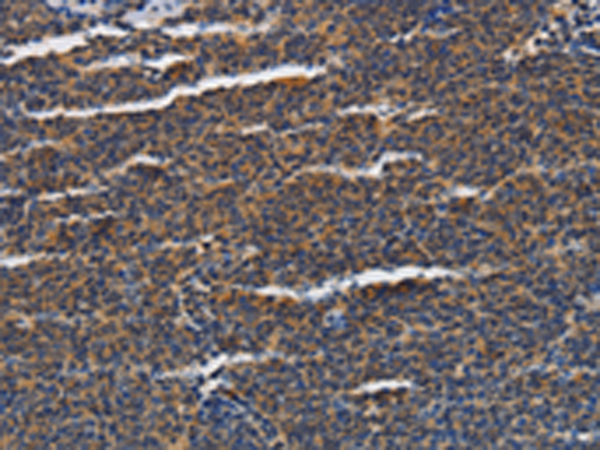

分类: 科研抗体货号: P04663别名:应用: WB,IHC反应种属: Human, Mouse, Rat